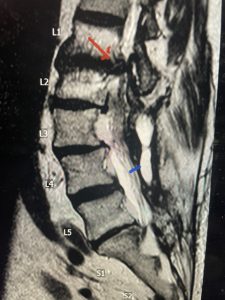

The next patient is a 71 year-old male with a two-year history of low back pain and lower extremity pain, numbness and weakness. His left leg was worse than the right. He had had five epidurals with no improvement. He also had tried physical therapy and medicines but nothing helped. He also felt that over the last three weeks he had gotten worse. He also had recently had some decreased sensation of bladder fullness and difficulty with bowel movements. MRI revealed a very tight L2-5 stenosis with an extruded L3-4 disc fragment (Fig 3).

(Figs 3a) Sagittal (a) and Axial (b) T2-weighted lumbar MRI demonstrating severe spinal stenosis L2-5 (arrow)and extruded disc at L3-4 on axial image (arrow)

(Fig 3b)

He had concentric severe stenosis with severe compression of the lateral recess and foramen at L3-4 secondary to the superimposed disc herniation. The fact that he had gotten worse with subtle cauda equina features with an extremely tight canal, he underwent a decompressive laminectomy. We also augmented his laminectomy with an in situ fusion from L3-5 as he was relatively young, with more time to reform arthritis, and had been unstable enough to extrude a disc fragment. By placing “bone dust” or bone material along the sides of the spine, specifically laying it across the transverse processes after they have been drilled to bleeding bone, you provide an environment where bone formation is induced to connect the segments, stabilize them, and thereby reduce the signal to make more arthritis as that signal is still present despite the laminectomy. What was interesting was that we encountered a large extruded disk fragment that was significantly contributing to his compression which is often not found in patients in this age bracket. Post operatively he had much improvement of leg pain.